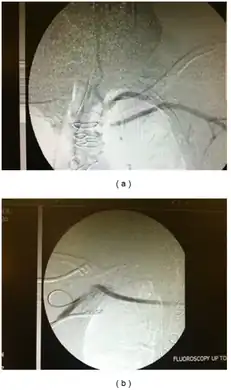

-

Restoration of flow in the left subclavian artery across a propaten graft from the right subclavian artery. -

Angiogram of subclavian steal phenomenon before and after stent placement